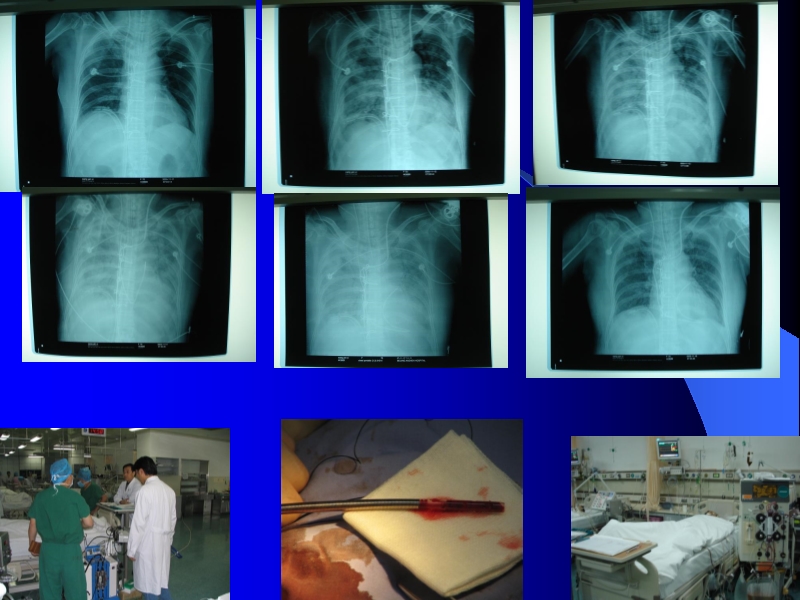

2006-11-17应用T-PLS治疗围手术期心衰的临床体会